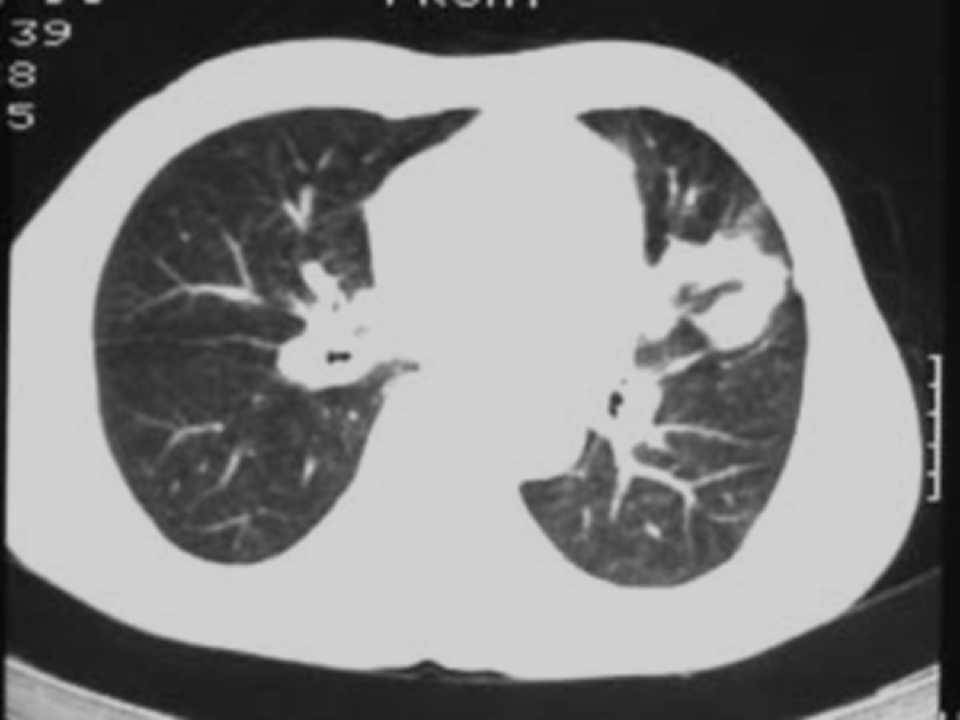

肺癌影像学表现